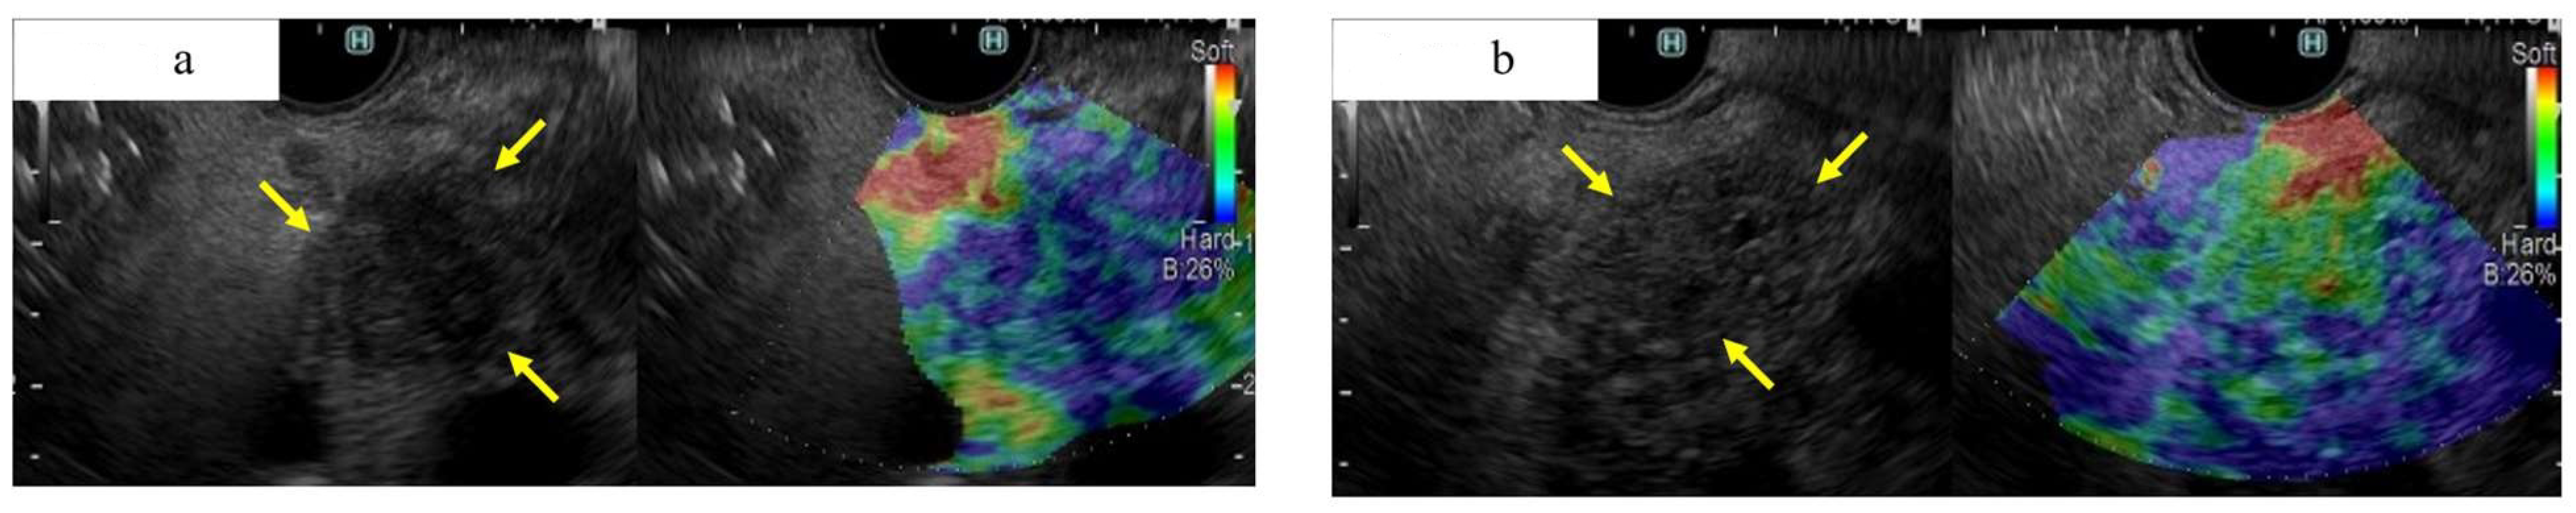

Figure 6.

A case of small ductal carcinoma of the pancreatic tail, imaged as a hard mass by EUS elastography (a), and a case of autoimmune pancreatitis of the pancreatic tail, imaged as a soft mass by EUS elastography. (a) Fundamental B-mode of EUS showing a 13 mm well-defined hypoechoic mass with irregular contours in the tail of the pancreas (yellow arrow). This tumor was shown to be a hard tumor on EUS-EG and was diagnosed as PDAC surgically. (b) Fundamental B-mode of EUS showing a 15 mm hypoechoic mass with an indistinct border and irregular outline in the tail of the pancreas (yellow arrow). This tumor was shown to be a relatively soft tumor on EUS-EG and was diagnosed as autoimmune pancreatitis by EUS-FNA.